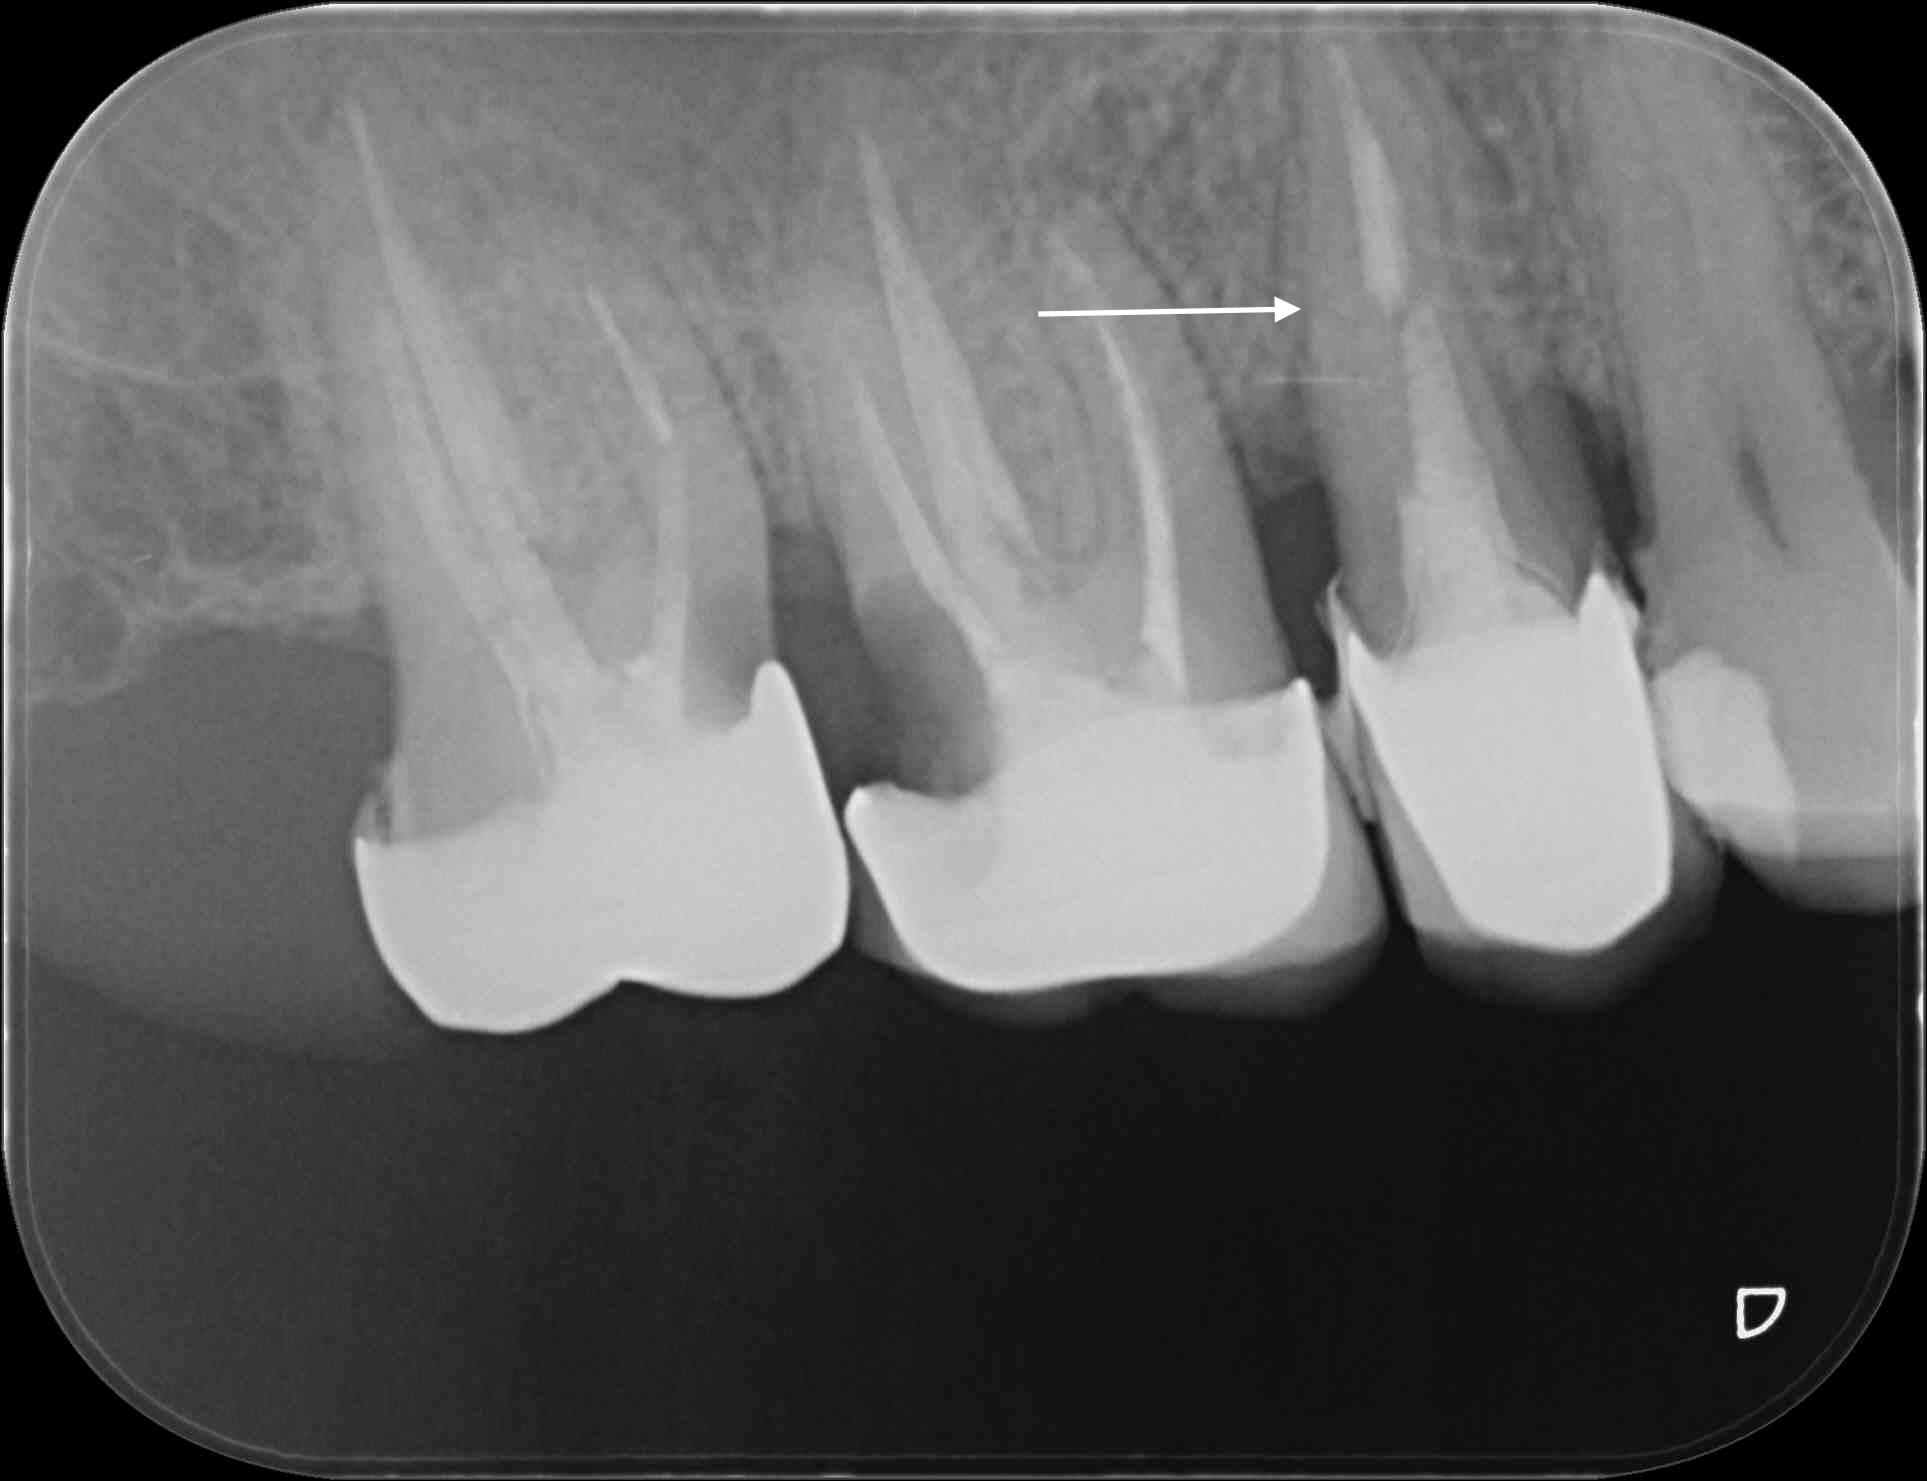

Patient 50 ans, parodontite chronique, venu consulter pour sa 15 mobile.

Que préconiseriez vous?

ce qui m'ennuie les plus c'est la lime cassée en mésial de 17 et l'image apicale et l'épaississement desmodontal

Bon évidemment, on a juste une rétro, c'est un peu léger, mais je ne vois pas d'indication d'extraction ici.

Radiologiquement j'ai des doutes....

Ferais bien un cone beam la....

la parodontite a peut être ( on n'a qu'une petite rétro ) seulement cette étiologie iatrogène, la dépose des coiffes montrera l'énormité du bourrage.

La 15 mobile, elle aurait pas une petite pète de racine ?

Elle n'est pas un peu fracturée cette racine ? J'ai l'impression de voir un trait de fracture

et moi j ai l impression de voir une carie sur 16 (et même 17) , et du coup , on commence par quoi ?